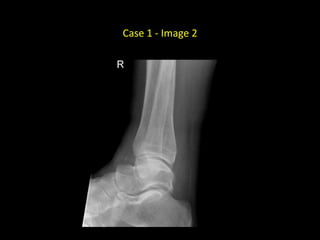

Case 1 - Image 2

• AP and lateral radiographs of

the right ankle in a skeletally

mature patient

• There is an oblique, non-

displaced fracture of the

distal shaft of the right tibia